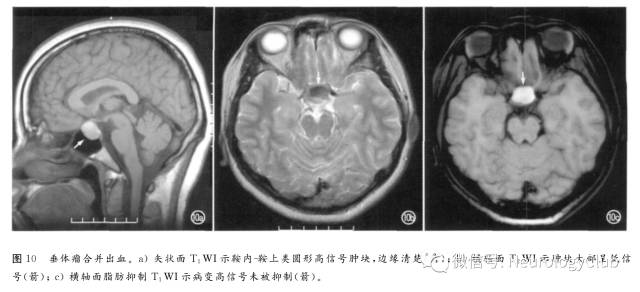

①垂体瘤:囊变、出血、坏死常见于10mm以上者,急性出血可导致肿瘤快速增大及压迫视交叉和垂体其余部分,出现急性视力下降及内分泌功能异常,并伴头痛,称垂体卒中,溴隐亭治疗者出血发生率增加;亚急性期MRI表现为T1WI高信号,脂肪抑制无信号下降(图10),随访可见病变缩小及囊腔形成。主要应与Rathke裂囊肿及颅咽管瘤鉴别。②胶质瘤:间变性星形细胞瘤、多形性胶质母细胞瘤(图11、12)和少突胶质瘤(图13)易出血,尤其是镜下可见的出血。③其它肿瘤如淋巴瘤(图14)、室管膜瘤(图15)与室管膜下瘤、髓母细胞瘤(图16)、血管母细胞瘤(图17)、原始神经外胚层肿瘤(图18)、表皮样囊肿及神经源性肿瘤,甚至少数脑膜瘤(图19)也可继发出血,形成瘤内T1WI高信号、甚至囊液-血液平面。